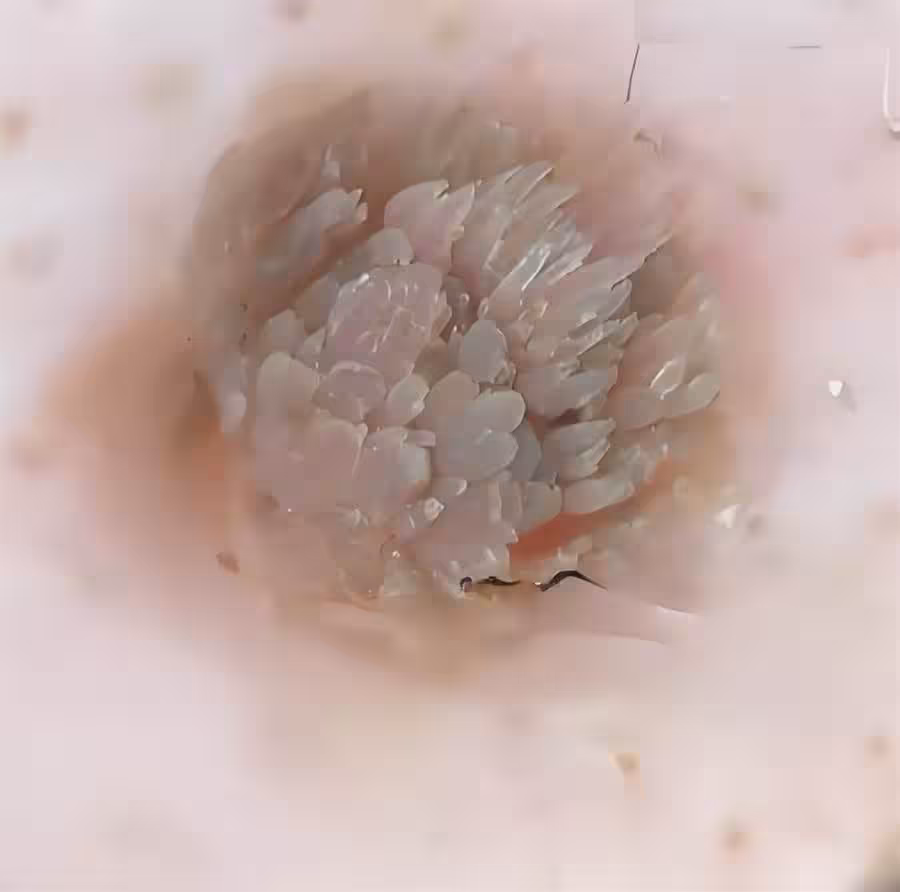

女子旅遊回來手上突現「菜花」硬塊!剪開瞬間嚇懵,醫生急喊:酒店這些「隱形雷區」打死別碰!